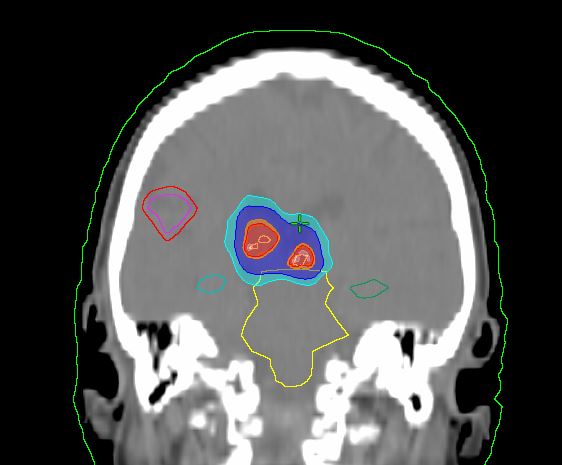

Пример плана лечения

- Очаг 1: Метастаз мелкоклеточного рака лёгкого в правой височно-теменной доле, размер 16×12×14 мм — 27 Гр за 3 сеанса

- Очаг 2: Метастаз в правом таламусе, размер 5.5×8 мм — 15 Гр за 1 сеанс

- Очаг 3: Метастаз в покрышке четверохолмия, размер 5×6 мм — 15 Гр за 1 сеанс

Целевой объём для планирования (ЦОП) формировался с геометрическим расширением на 1–2 мм. Дозы подбирались с учётом расположения очагов и близости критических структур. Облучение проводилось с использованием нескольких некомпланарных динамических арок на линейном ускорителе Varian TrueBeam с энергией фотонов 10X-FFF.